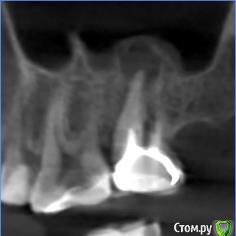

anafree Опубликовано 25 февраля, 2016 Поделиться Опубликовано 25 февраля, 2016 (изменено) Добрый вечер! Подскажите, пожалуйста, возможно ли попробовать перелечить, удалить кисты без удаления зубов? То что дорого, знаю. Интересует, есть ли возможность вообще в данной ситуации. Две верхние семерки, там стоят вкладки и коронки (стоят уже лет 10) и нижняя 7-ка, там пока временная коронка на штифте просто стоит. Ни один из трех зубов не беспокоит. Изменено 25 февраля, 2016 пользователем anafree Ссылка на комментарий

DmitrySH Опубликовано 26 февраля, 2016 Поделиться Опубликовано 26 февраля, 2016 Да, можно спасти, но возможно что не все, для полноценного ответа нужно больше снимков. И то, на снимках всего не видно. Чем качественнее сделаны вкладки, тем сложнее их извлекать. Ссылка на комментарий